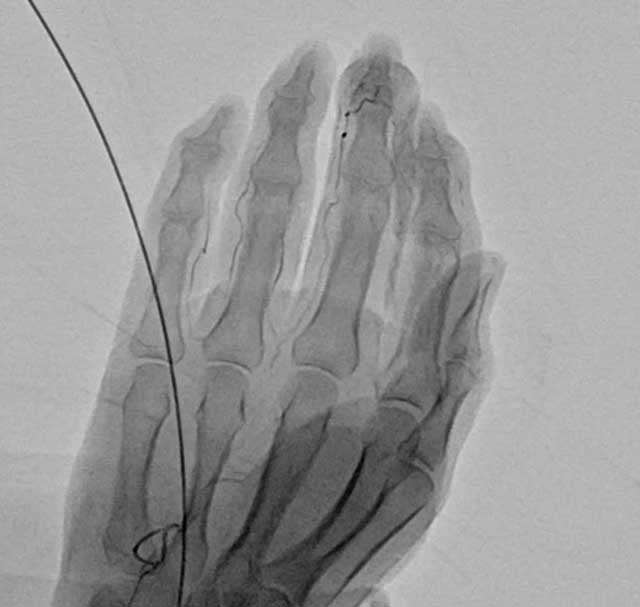

簡易動注療法は、エコーで血管を確認しながら、手首や足首などの動脈に薬剤を注入する治療です。

痛みの原因となる「モヤモヤ血管」と呼ばれる異常血管を一時的に塞ぐことで炎症を鎮め、慢性的な痛みを軽減します。